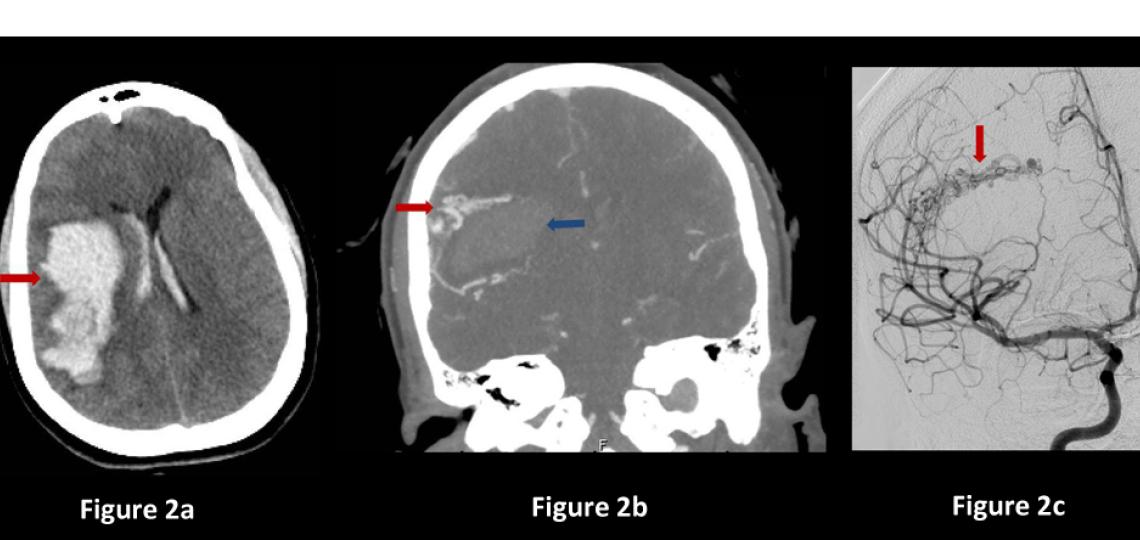

Neurosurgery is often the best option for small to medium size AVMs in favorable areas of the brain because it allows for the immediate and complete cure of the AVM, with a good safety profile. The patient undergoes traditional surgery in the operating room under anesthesia. An angiogram during surgery can confirm that the AVM is removed, and there is no longer a risk of bleeding from it. Neurosurgery provides an immediate cure (Figure 3).

Figure 3a: MRA scan showing right frontal AVM (arrow). Figure 3b: CT scan after surgery showing no remaining AVM (arrow). Figure 3c: Brain angiogram before surgery showing the brain blood vessels and large AVM (black mass). Figure 3d: Brain angiogram after surgery showing normal brain vessels and no AVM.